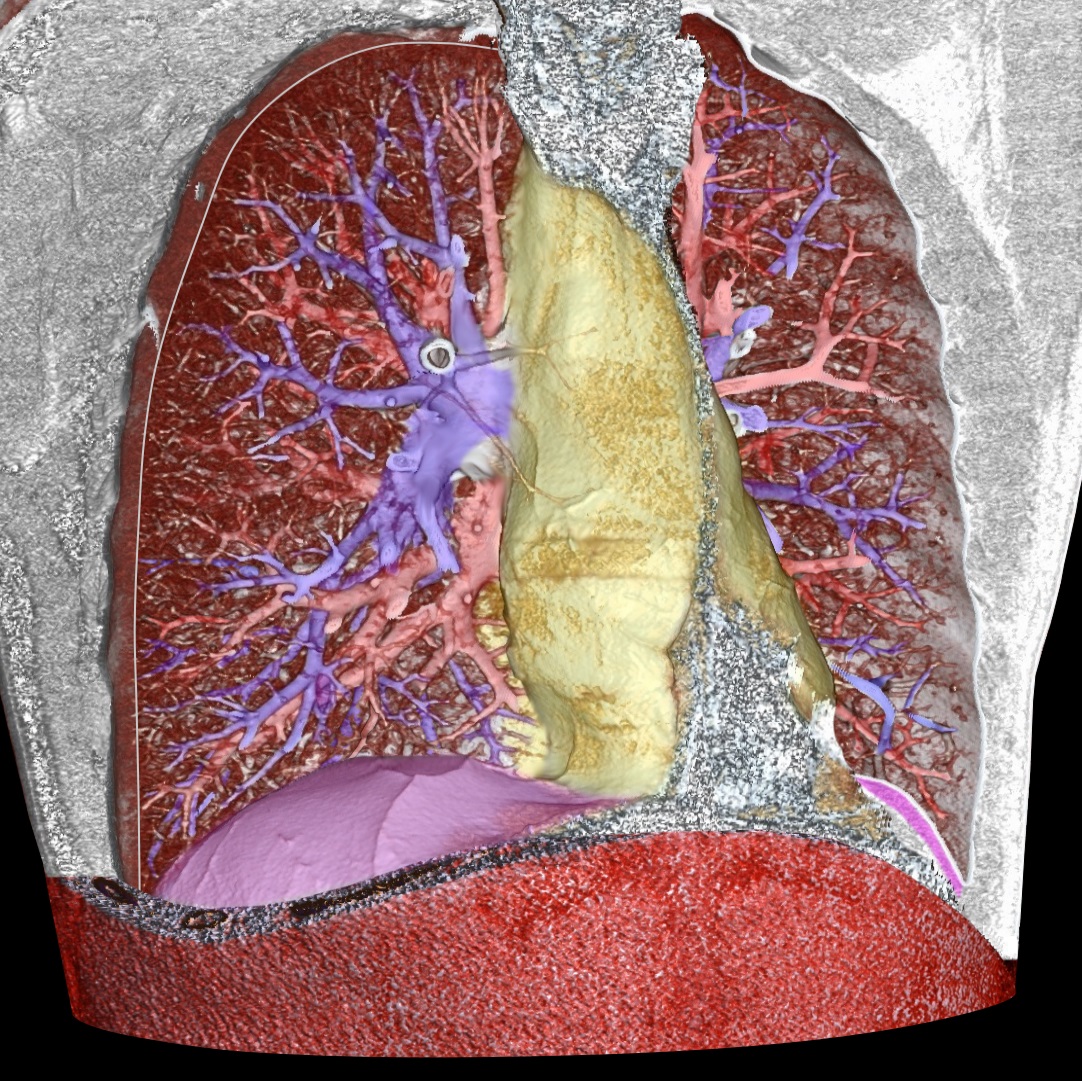

볼륨 렌더링은 3차원 볼륨 데이터를 2차원 이미지로 시각화하는 기술로, 의료 영상, 과학 시각화, 엔지니어링 등 다양한 분야에서 활용된다. 렌더링 방식으로는 직접 볼륨 렌더링, 볼륨 레이캐스팅, 스플래팅, 시어 워프, 텍스처 기반 볼륨 렌더링 등이 있으며, 특히 직접 볼륨 렌더링은 불투명도와 색상을 전송 함수를 통해 픽셀에 투영하는 방식이다. 최적화 기술로는 빈 공간 건너뛰기, 조기 광선 종료, 옥트리 및 BSP 공간 분할, 볼륨 분할, 다중 및 적응 해상도 표현, 사전 통합 볼륨 렌더링 등이 사용되며, 하드웨어 가속을 위해 GPU가 활용되기도 한다. 볼륨 렌더링을 지원하는 소프트웨어로는 3D Slicer, ParaView, Vaa3D, VTK 등 다양한 오픈 소스 및 상용 프로그램이 있다.

볼륨 렌더링은 얇은 단면 단층 촬영 프레젠테이션이나 최대 강도 투영을 포함한 3D 모델의 투영과는 구별된다.[1] 하지만 기술적으로 모든 볼륨 렌더링은 2차원 디스플레이에 표시될 때 투영이 되므로, 이 둘의 구분이 다소 모호하다. 그럼에도 불구하고 볼륨 렌더링 모델은 현실적이거나 관찰 가능한 표현을 만들기 위해 색상[2]과 음영[3]을 혼합하여 특징을 나타낸다.

볼륨 렌더링은 얇은 단면 단층 촬영 프레젠테이션과 구별되며, 최대 강도 투영을 포함한 3D 모델의 투영과도 일반적으로 구별된다.[1] 하지만 기술적으로 모든 볼륨 렌더링은 2차원 디스플레이에서 볼 때 투영이 되므로, 투영과 볼륨 렌더링의 구분이 다소 모호하다. 그럼에도 불구하고 볼륨 렌더링 모델의 전형적인 예는 현실적이거나 관찰 가능한 표현을 만들기 위해, 예를 들어 색상[2]과 음영[3]을 혼합하여 특징을 나타낸다.